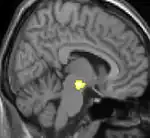

Positron emission tomography (PET) scans indicate the brain areas which are activated during attack only, compared to pain free periods. These pictures show brain areas that are active during pain in yellow/orange color (called "pain matrix"). The area in the center (in all three views) is specifically activated during CH only. The bottom row voxel-based morphometry (VBM) shows structural brain differences between individuals with and without CH; only a portion of the hypothalamus is different.[33]